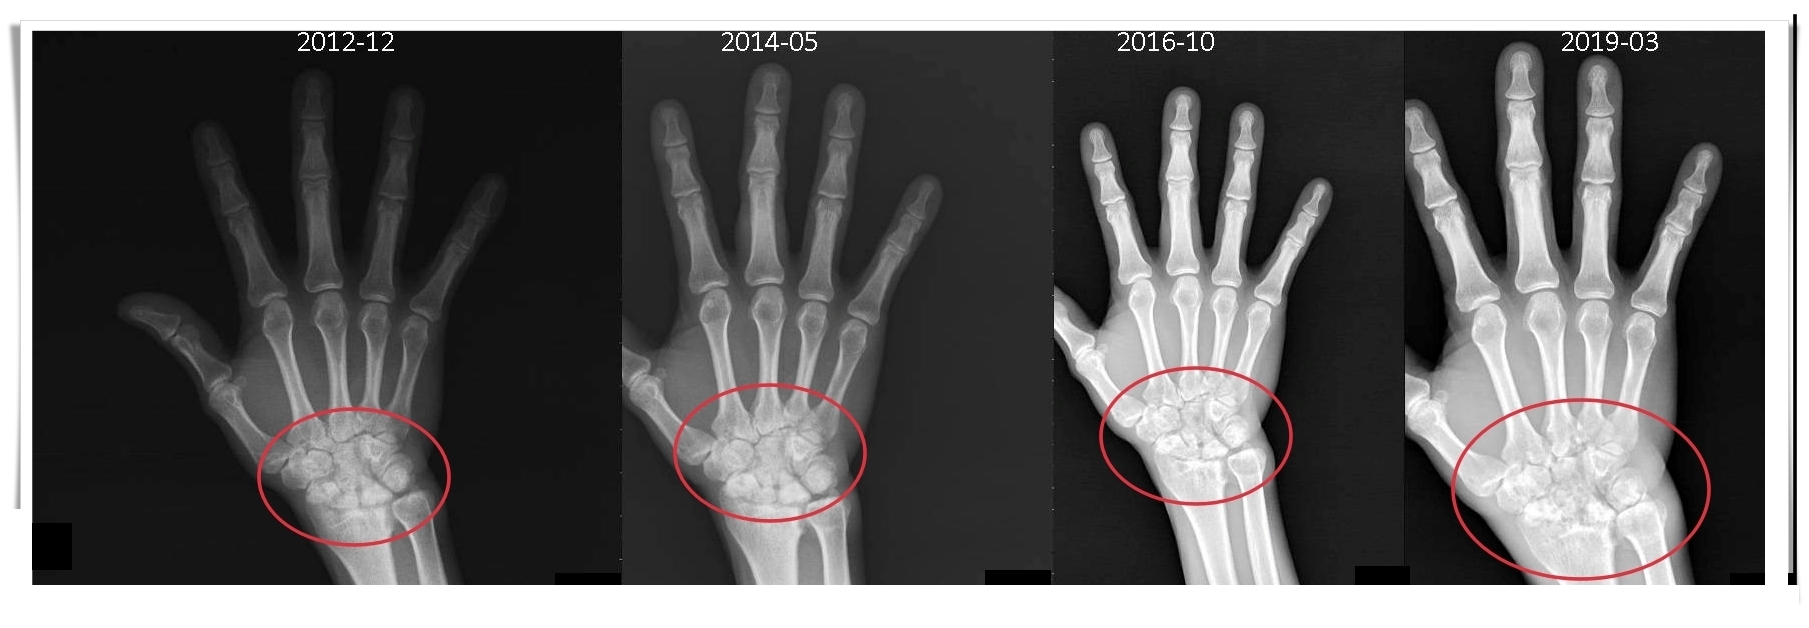

以張先生為例,他的發炎指數雖然正常,但手部關節內部已經悄悄被破壞。這種「骨侵蝕」是不可逆的情形,若置之不理,最後甚至可能會造成手部變形、無法正常握持工具,嚴重影響生活與工作品質。經比對患者近年來的X光檢查影像,發現確實已經出現異常,於是改用另款新型生物製劑治療後,關節破壞程度才穩定放緩,目前已經恢復原本的生活步調。

▲ 患者手腕關節的變化或許每年都不顯著,但長期來看,

黃柏豪強調,類風濕性關節炎的最大問題不只是「痛」而已,而是關節破壞常在無聲無息中發生,導致患者會認為病情趨緩,因而降低警戒,等到發現症狀惡化時,往往已經難以回頭,短時間實在難以察覺。